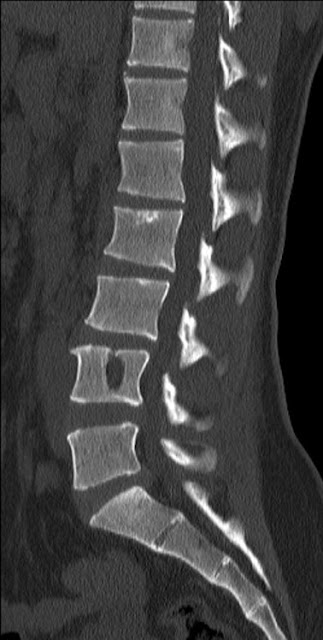

Mri dorso lumbar region spine sagittal t2w images show: For most patients, scheuermann's disease runs a fairly benign course, with resolution of symptoms at skeletal maturity. Scheuermann, or scheuermann's, disease (juvenile kyphosis) is a deformity in the thoracic or thoracolumbar spine in which pediatric patients have an increased kyphosis along with backache and localized changes in the vertebral bodies. How do you get schmorl's nodes? Schmorl's nodes and modic changes (endplate mri signal change) on lumbar mri, back pain and physical function restrictions seem to be more prevalent among patients with scheuermann's disease. Most can form after a heavy loading incident or trauma which forces the nucleus part of the disc through the endplate instead of the outer part of the disc. Associated with irregular vertebral endplates, schmorl nodes, and loss of disc space height noted on sagittal imaging studies. This commonly results in back pain and is usually managed medically. Mri dorso lumbar region spine sagittal t2w images show: Schmorl's nodes are disc herniations in the spinal bone which are usually not painful. Scheuermann's disease describes a condition where the vertebrae grow unevenly with respect to the sagittal plane; The upper and middle areas of the spine, called the thoracic spine, consist of the 12 vertebrae below the seven that make up the cervical spine. Range of motion:the physician assesses the degree to which the patient can bend forward, back, and side to side. All had various disk problems including scheuermann's disease, schmorl's nodes and limbus vertebrae. With the help of some of the bravest and strongest people in the world, we, at the scheuermann's disease fund, have created a video project to let people know what it is like to live with scheuermann's disease, especially as we. In 1964, sorensen introduced the classic diagnostic criteria for sd of three consecutive vertebral bodies with anterior wedging of at least 5 degrees.5 additional imaging findings include endplate irregularities, commonly manifested as schmorl's nodes. Scheuermann's disease is a developmental disorder of the spine that is caused by abnormal growth of the vertebrae. Multiple and contiguous involvement of vertebral bodies, the anterior wedging, antero posterior elongation, associated schmorl's nodes, end plate irregularity and disc space narrowing. Small disc herniations through the endplates of the vertebrae (called schmorl's nodes). @article{swischuk1998diskdd, title={disk degenerative disease in childhood: Familial scheuermann disease is characterized by kyphotic deformity of the spine that develops in adolescence. Scheuermann's disease, schmorl's nodes, and the limbus vertebra: So scheuermann's disease inheritance remains uncertain, especially as these studies were based on restricted data coming from a few pedigrees. It affects less than one percent of the population and occurs mostly in children between the ages of 10 this forms pockets of disc material inside the vertebral body, a condition called schmorl's nodes. Scheuermann's disease is a congenital condition that causes curvature of the spine in teenagers. The diagnosis is usually made on plain film. Scheuermann kyphosis, also known as scheuermann disease, juvenile kyphosis or juvenile discogenic disease, is a condition of. 14 evidence of increased pain, suspicion of rapid progression, and/or neurologic compromise. Descriptions of schmorl's nodes note they generally do not cause many problems and they are in fact a pretty common side effect of general wear and tear on the spine. Scheuermann's disease causes some od the spinal vertebrae to grow in a wedge shape instead of a normal cylindrical shape. When scheuermann's disease is present, the thoracic area of the spine is overly curved from the side.

Scheuermann's Disease Schmorl's Node - Associated With Irregular Vertebral Endplates, Schmorl Nodes, And Loss Of Disc Space Height Noted On Sagittal Imaging Studies.

Scheuermann's Disease Schmorl's Node . Multiple And Contiguous Involvement Of Vertebral Bodies, The Anterior Wedging, Antero Posterior Elongation, Associated Schmorl's Nodes, End Plate Irregularity And Disc Space Narrowing.